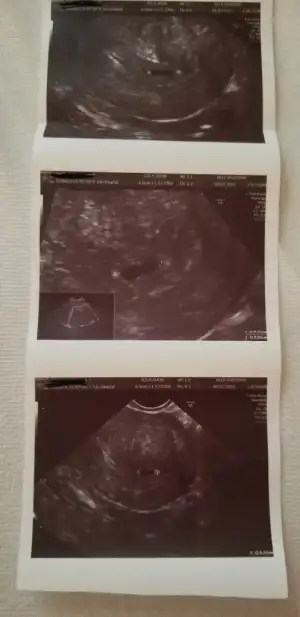

Kese içinde parlak bişey vardı ama yolk sanırım soramadım heyacan dan kalp atışı ve bebek için erken dedi canım 8 hafta için randevu verdi ama ben bi 7ci hafta da gidicem😊

Bende bugün keseyi gördüm. Bebeği görmek için çok erken dedi. 7. Haftada gel dedi.

• 20210710_095143.webp

20210710_095143.webp

41,4 KB · Görüntüleme: 81